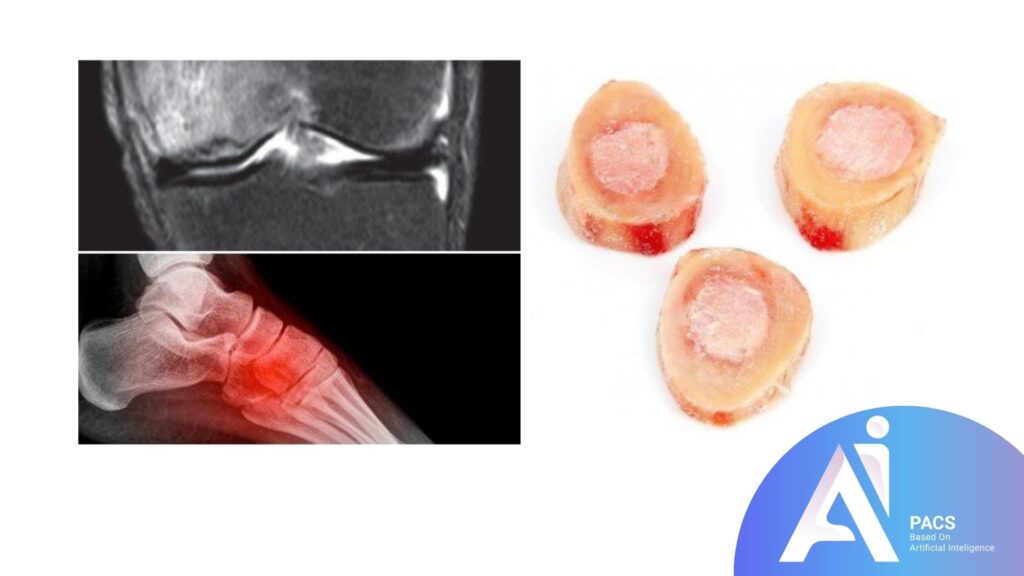

How is Bone Marrow Edema Detected on MRI?

MRI (Magnetic Resonance Imaging) is the most effective imaging modality for detecting bone marrow edema (BME) due to its ability to provide detailed images of soft tissues, including the bone marrow. It is particularly sensitive to changes in fluid content, making it ideal for identifying edema.

Description of what BME looks like on an MRI scan

On an MRI scan, bone marrow edema is typically seen as areas of increased signal intensity (brightness) on T2-weighted or STIR images. The brighter appearance is due to the accumulation of fluid within the bone marrow. In contrast, normal bone marrow has a more uniform, lower-intensity signal. The exact location of the edema on the scan can vary, but it usually correlates with the site of injury, inflammation, or degeneration.

- Location: Bone marrow edema can appear in any bone, but it is most commonly found in weight-bearing joints (e.g., knees, hips, ankles) or bones affected by trauma or degenerative conditions.

- Signal Characteristics: Edema appears as a bright, patchy, or diffuse area, often near a site of injury (e.g., fractures, ligament tears), or within joints in cases of arthritis or other conditions.

The ability of MRI to detect and differentiate between normal and edematous bone marrow helps physicians diagnose the underlying cause and guide treatment decisions more accurately.

X-rays

While X-rays cannot detect bone marrow edema, they are useful in identifying fractures, bone deformities, or signs of osteoarthritis that may be causing the edema. X-rays are often the first imaging test ordered, especially after trauma.